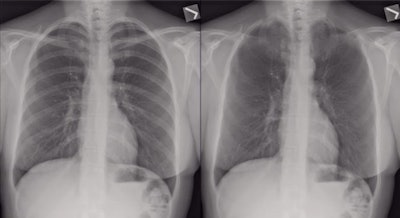

The technique is bone suppression imaging, in which a postprocessing bone suppression algorithm can be used to suppress the conspicuity of bones on chest radiographs to create corresponding bone suppression chest images.

Left, chest radiograph; right, bone suppression. Image courtesy of Dr. Yun Wang.Left, chest radiograph; right, bone suppression. Image courtesy of Dr. Yun Wang.